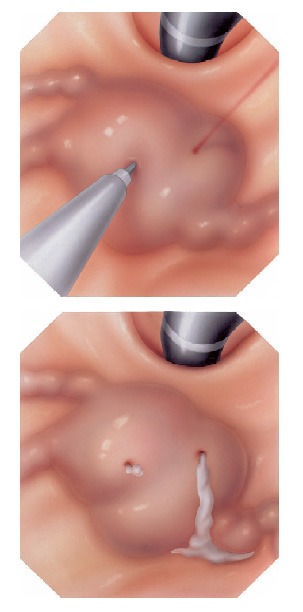

Mucosectomia é o procedimento realizado quando há necessidade de retirada de lesões maiores do trato gastrointestinal.

O exame de Mucosectomia é realizado através de injeção de liquido embaixo da lesão, através de uma agulha específica. Com isso a lesão se destaca das camadas mais profundas do intestino, diminuindo o risco de perfuração.

A retirada da lesão é feita com uma alça de polipectomia e o material é encaminhado para estudo anatomopatológico (no microscópio) da mesma forma que ocorre nas biópsias.

Mucosectomia

Para diminuir este risco, injeta-se com um uma agulha uma solução abaixo do pólipo para que ele levante e fique mais longe da parede do órgão. Após isto passa-se a alça diatérmica e realiza-se o

procedimento de polipectomia.